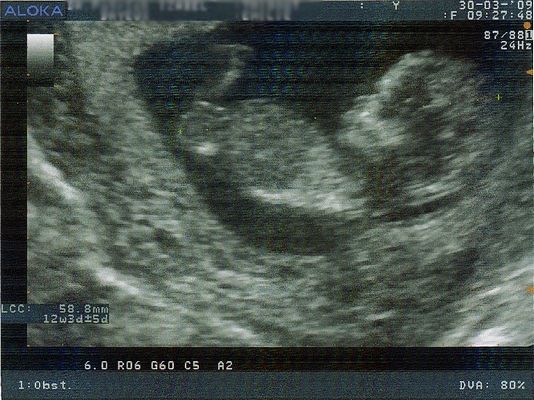

| Dire merci | Coucou les filles J'ai fais l'écho des 3 mois ce matin, même si officieusement les 3 mois seront le 18 Avril. Petit récap': le 6 Mars bout de choux faisait 2 cm aujourd'hui il en fait 6 ![]() Il a ses p'tits bras, p'tits pieds, tout va pour le mieux, comme m'a dit le gygy, il danse déjà la rumba sa nuque fait 1,2 mm. Le 20 Avril je fais la prise de sang pour la trisomie 21... Devrait pas y avoir de problème, mais le risque 0 n'existe malheureusement pas. Par la même occasion je refais une prise de sang pour la toxo, étant donné que je ne suis pas immunisée je suis suivie... photo plus tard dans l'après midi ![]() |

| Dire merci | Voilà notre trésor, 6 cm de vivacité ![]() prochaine écho le 27 Avril, rendez vous avec la sage femme le 5 Mai, et je vais me mettre au chant prénatal!! qui connait? ![]() |

| Dire merci | emy50 : ouaaa !! j'adore comme on voit bien la ptite tête déjà ! candia : pour les photos !! kalimero ... bah courage lol ! on est dans le même bateau !!! gandhi : je croise les doigts pour toi ! ! |